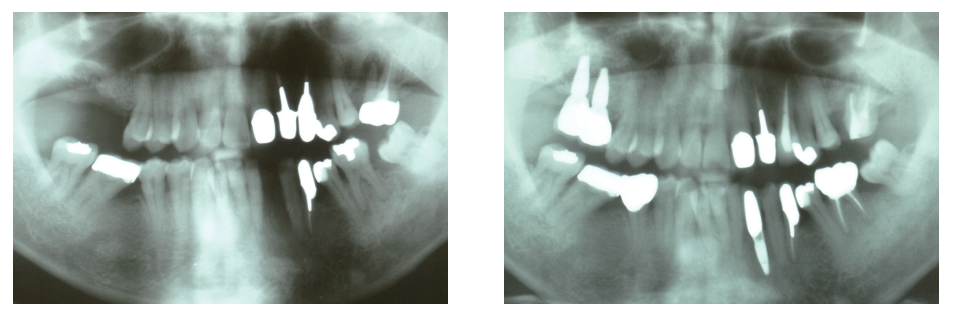

歯科インプラント治療は、顎骨にチタン製の金属(インプラント体)を埋め込み、その上に人工歯(上部構造)を装着することで咬合機能を回復する治療です。当科では、骨量が不足しており骨増生手術が必要な難症例に対しても、人工骨を使用することによって低侵襲に歯科インプラント治療を行います。CT検査を行い、手術シミュレーションソフトを用いた治療計画により、安全性の高い治療を提供します。

人工骨を用いて骨増生手術を行った歯科インプラント治療(左:術前、右:術後)

最新 骨補填材料&メンブレンYEARBOOK2021/2022 藤田記述箇所より引用